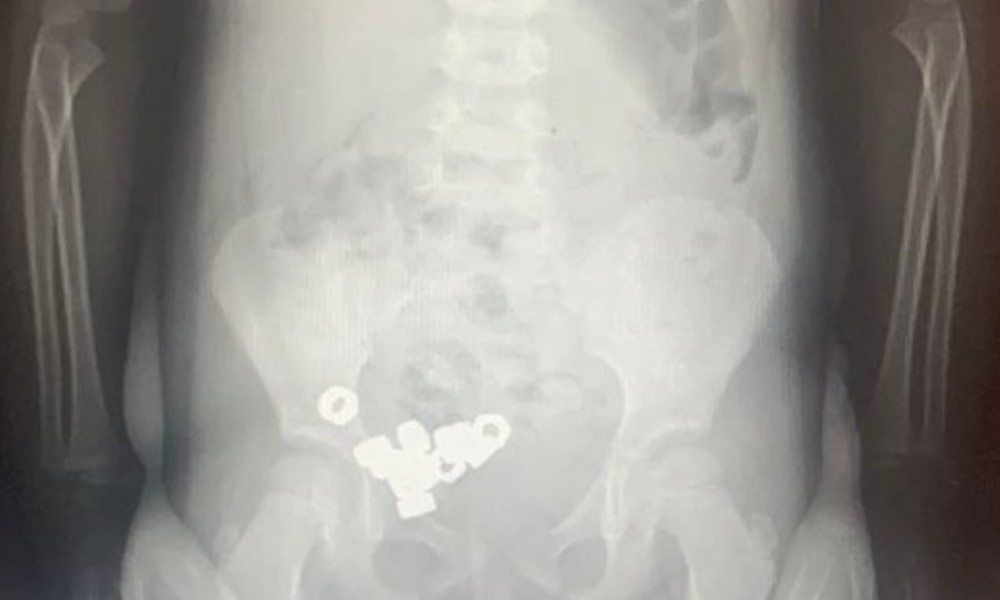

В Воронеже врачи спасли проглотившего 16 металлических гаек трёхлетнего ребёнка

Врачи областной детской клинической больницы №2 помогли трёхлетнему мальчику, который проглотил шестнадцать маленьких гаек. Об этом сообщили в министерстве здравоохранения Воронежской области.

Родители привезли ребёнка в приёмное отделение, заподозрив, что он мог проглотить что-то постороннее. Симптомов не было, малыш чувствовал себя спокойно, но врачи сразу направили его на рентген. Снимок показал десятки чётких контуров металлических предметов – в желудке и кишечнике находилось 16 гаек.

Мальчика оставили в больнице под наблюдением. Опасность состояла в том, что инородные предметы могли вызвать травмы или закупорку. Врачи выбрали щадящий способ – без операций: назначили диету, отдых и постоянный контроль. Каждый день ребёнку делали рентген, чтобы убедиться, что гайки постепенно выходят естественным путём.

К счастью, уже на третий день все предметы покинули организм без последствий. После этого мальчика выписали домой.